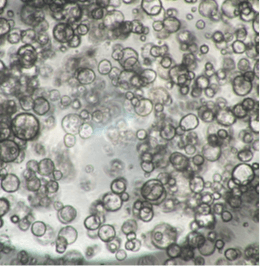

InnoCell(R)プレートシリーズは、体外での細胞培養において、各々の細胞に適した酸素供給を実現できます。その機能により、長期間、元気な細胞を体外で培養できるうえ、スフェロイドの内部で起こる壊死を軽減できるため、正確な医薬品のスクリーニング結果の提供に期待されています。また、これまで体外で培養が難しかった、ヒト膵がん患者由来オルガノイドの増殖性の向上により、個別化医療における患者さんに適した医薬品の早期提供の可能性も期待されています。

さらに、プレートへの薬剤の吸着性が低く、ガラスに匹敵する蛍光観察性能を備えています。試験に供した薬剤が正確に細胞へ作用し、細胞の構造、機能などが可視化できる価値も認められています。